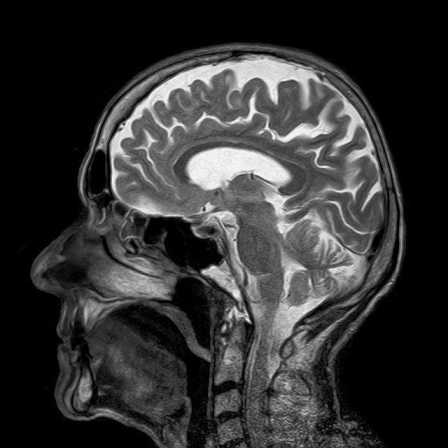

पेलीजेअस – मेंर्जबैकर डिजीज क्या हैं । Pelizaeus-Merzbacher Disease in Hindi Login to Health मार्च 19, 2021